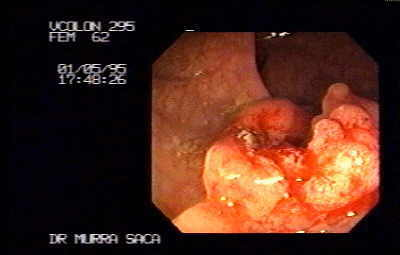

Cáncer rectal en la línea pectina:

El límite del ano con el recto, se nota que este tumor proviene de un pólipo que se ha degenerado. La teoría adenoma carcinoma. En esta región es suficiente el tacto rectal para detectar estos cánceres o pólipos. La mayoría de los cánceres aparecen por descuido de las personas al no tomar importancia de su salud.